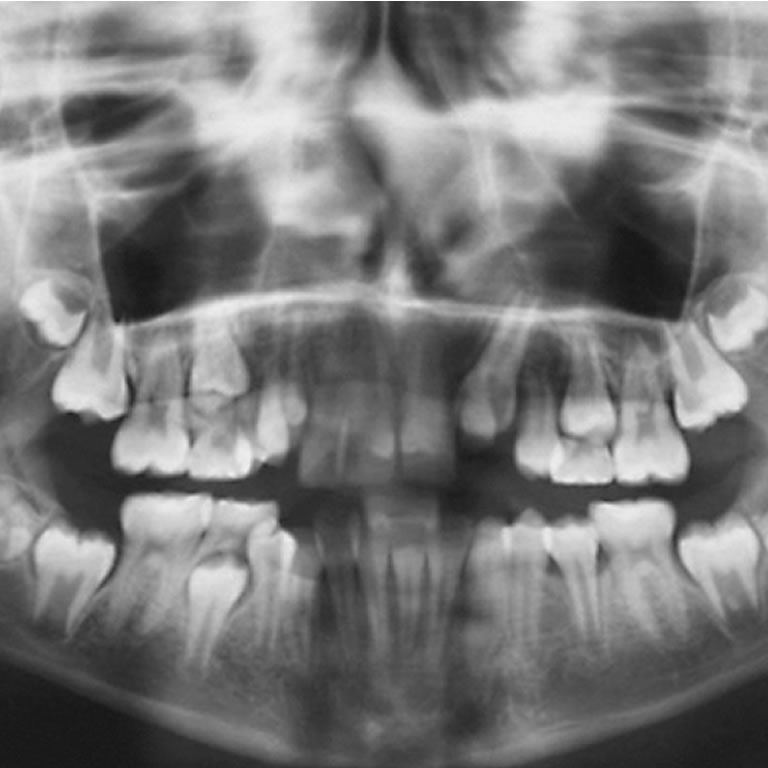

Avulsiones Dentarias

Beatriz Herbel

La avulsión dentaria es la salida completa del diente de su alvéolo, afectando pulpa, ligamento periodontal, cemento, encía y hueso alveolar. Suele acompañarse de lesiones en tejidos blandos y labios, por lo que requiere atención inmediata.